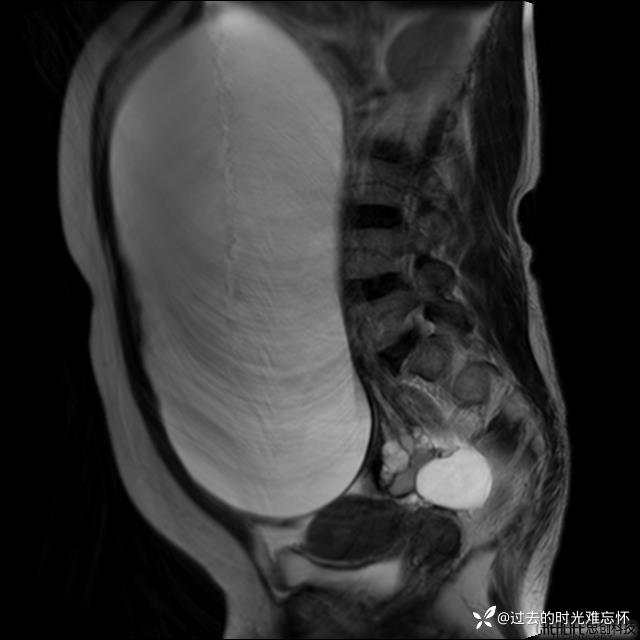

腹大能容5000液;术后腹部好轻松。妙手回春有结果。公布结果。

患者性别:女

患者年龄:65岁

主诉: 发现腹部隆起半年余。无其他明显不适。

浆液性囊腺瘤 (22)